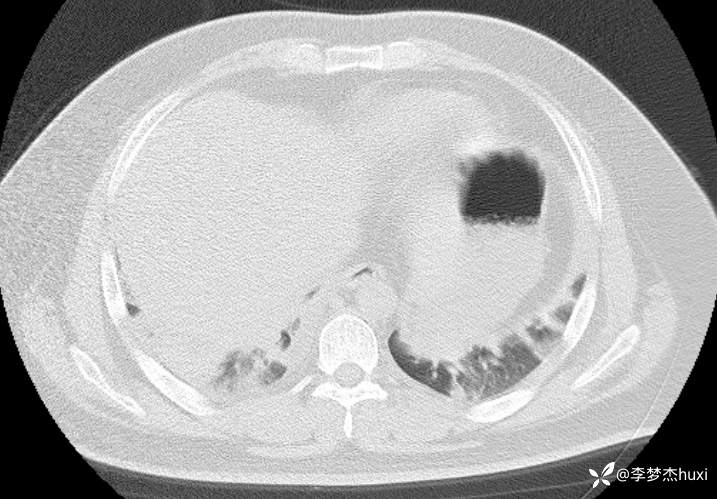

【现病史及既往史】: 1.患者青年 男,患者缘于2天前无诱因出现胸痛,为前胸痛,伴后背疼痛,咳嗽及深呼吸时明显,伴咳嗽,痰不易咳出,伴恶心、呕吐,伴发热,体温最高达37.7℃,无寒战,无咯血,院外未应用药物治疗,症状无明显好转,为求进一步治疗来院就诊,门诊查胸部CT提示:双肺炎症,较前进展,双肺纹理增重,右肺实性结节,建议随诊复查,双侧胸膜局部增厚,右侧胸腔少量积液。以“肺炎”收住院;。

【检查】: 4.辅助检查:心电图示:窦性心动过速,门诊查胸部CT提示:双肺炎症,较前进展,双肺纹理增重,右肺实性结节,建议随诊复查,双侧胸膜局部增厚,右侧胸腔少量积液。